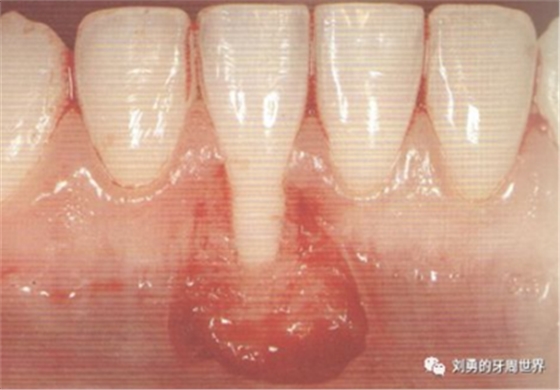

術(shù)前可見第一前磨牙膜齦聯(lián)合位于齦緣的位置,該牙位附著齦缺失,需要增寬附著齦。

對于需要進(jìn)行根面覆蓋的手術(shù),移植瓣需要縫合固定到CEJ冠向1mm左右的位置。如下圖: